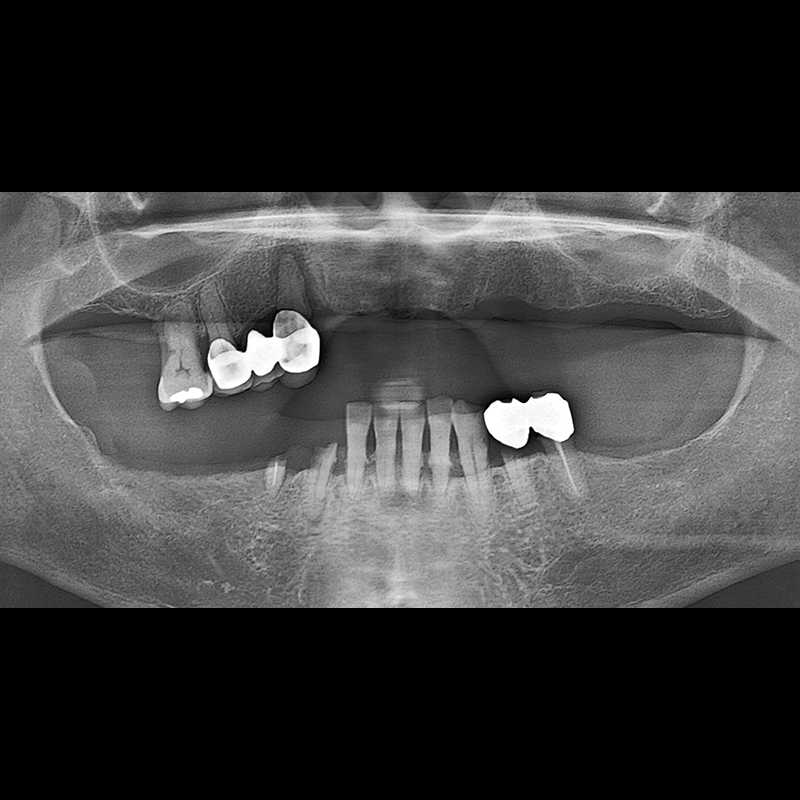

BEFORE AFTER

种植牙前后的照片 2025.05.30

在缺失的牙齿部分和难以挽救的牙齿位置植入了种植牙。